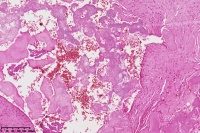

右胫骨内组织,单纯性骨囊肿?

性别

男

年龄

12岁

临床诊断

内生性软骨瘤?骨囊肿?

标本名称

右胫骨内组织

图3